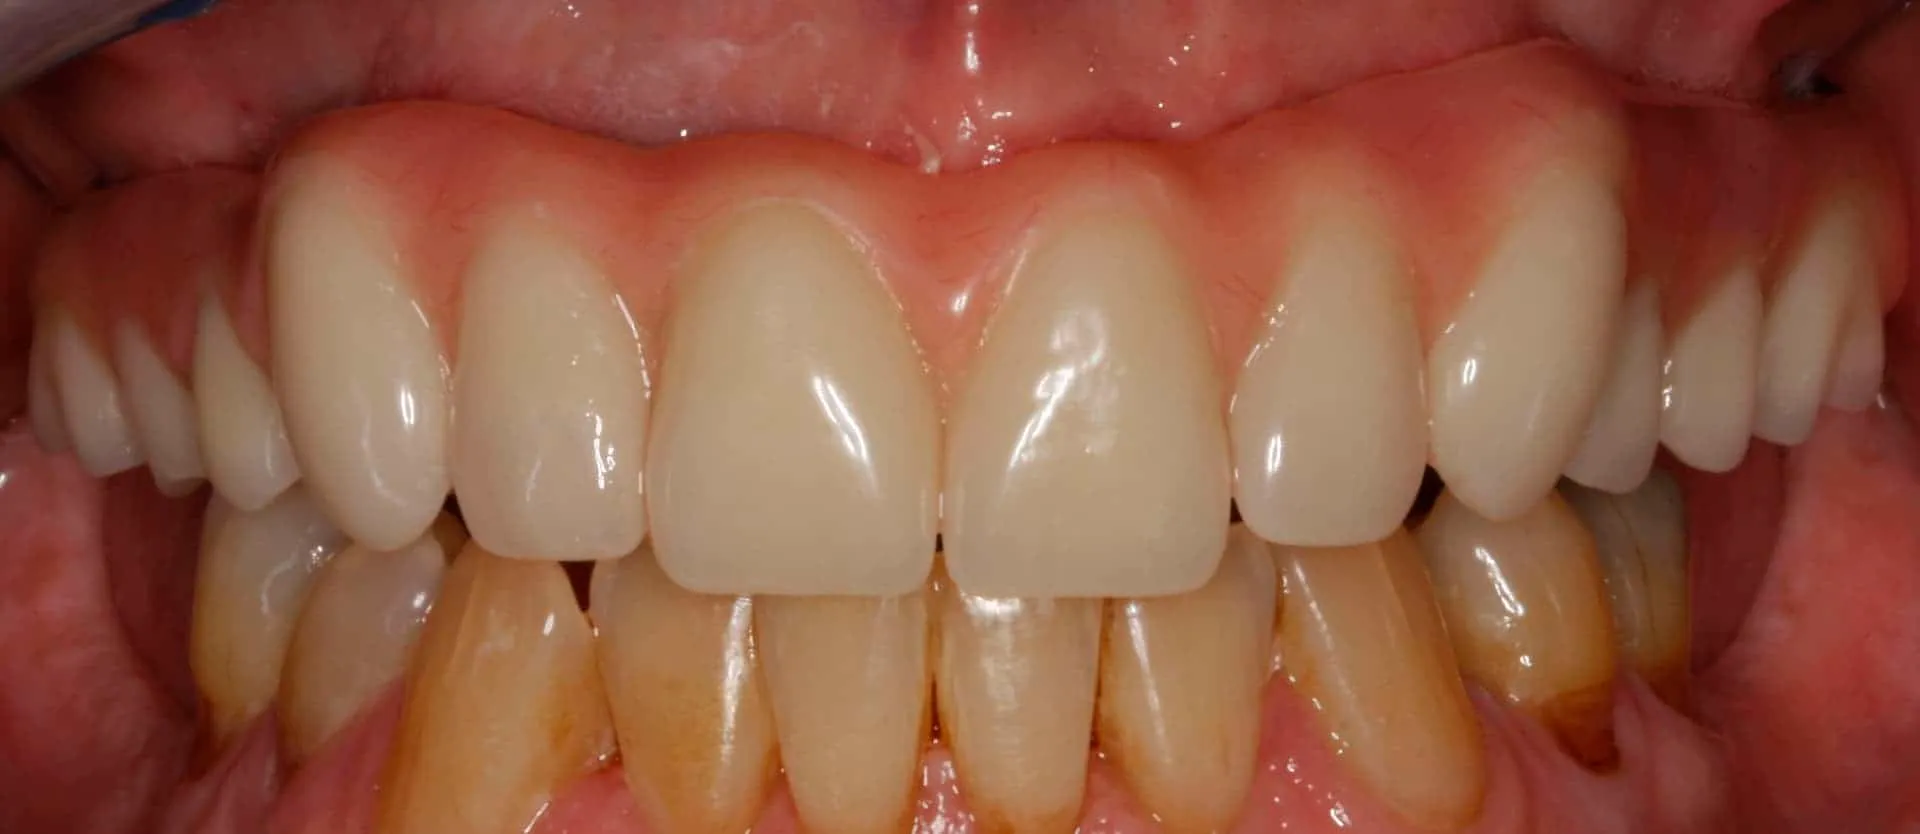

After: Maxillary (upper), acrylic fused to metal, fixed (hybrid) screw-retained (retrievable) restoration supported by 6 titanium root form dental implants. The restoration is fixed, therefore only Dr. Leopardi can remove it for routine maintenance and hygiene, as needed. The patient cleans the fixed restoration as he does his natural lower teeth, with a tooth-brush, floss and water-pick. The outcome is improved function, mastication/diet, aesthetics and quality of life.